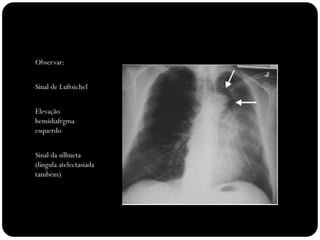

Observar:

Sinal de Luftsichel

Elevação

hemidiafrgma

esquerdo

Sinal da silhueta

(língula atelectasiada

também)

Atelectasia do lobo

inferior esquerdo